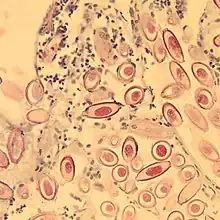

Eggs of Capillaria hepatica

- A taxonomic genus within the family Capillariidae – slender white nematode worms that include serious pathogens of the digestive tract of fowls and some tissue and organ parasites of mammals.